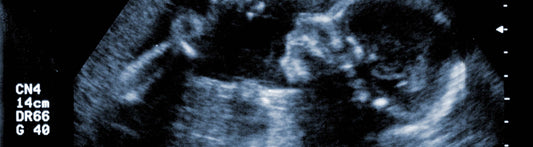

14 Weeks Pregnant: What to Expect as Your Baby ...

Congratulations on reaching 14 weeks pregnant! Your baby is growing rapidly, and you are likely experiencing a range of new symptoms and changes in your body. Here are some of...

14 Weeks Pregnant: What to Expect as Your Baby ...

Congratulations on reaching 14 weeks pregnant! Your baby is growing rapidly, and you are likely experiencing a range of new symptoms and changes in your body. Here are some of...